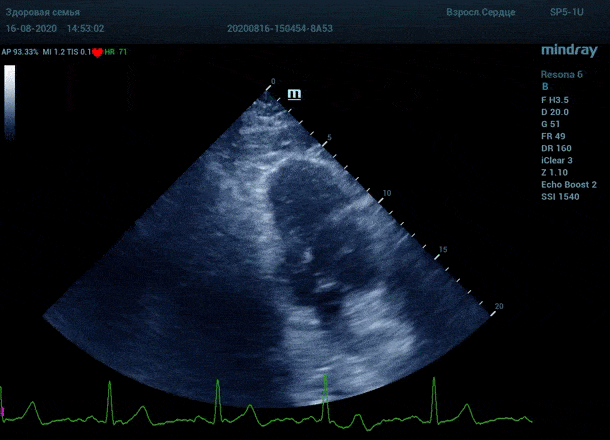

Глаз каждого человека по своей природе уникален. Одни люди лучше видят белый и серый цвет, прекрасно различают все его оттенки. Другим людям проще ориентироваться в голубом, синем и фиолетовом диапазоне, холодных тонах изображения. Однако большинство прекрасно видит оранжевый цвет, и очень четко отличает его от черного – анэхогенного пространства.

Адаптивный колорайзинг - настоящая находка для опытного врача ультразвуковой и функциональной диагностики. Для тренированного глаза открывается новый мир четких контуров, совершенно другой взгляд на привычные структуры сердца.

Данная функция присутствует в большинстве моделей Mindray, с возможностью эхокардиографического исследования. Ограниченное ЭХО окно можно победить разными путями.